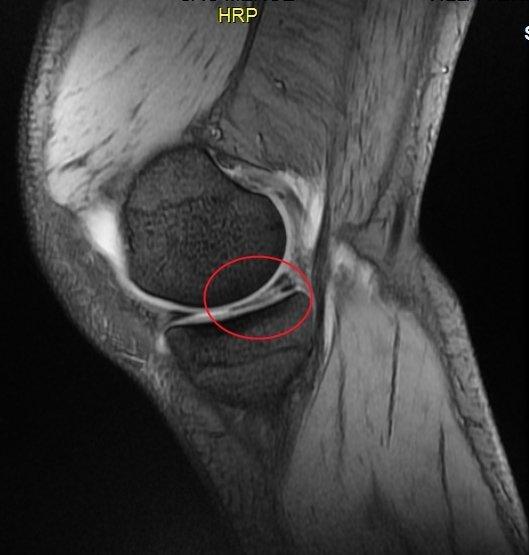

Les ménisques sont des fibrocartilages situés dans l’articulation du genou entre le fémur et le tibia. Il en existe deux par genou, un ménisque interne et un ménisque externe. Ils protègent les cartilages sus et sous-jacents des chocs et des excès de contraintes et sont ainsi de véritables amortisseurs du genou. Les ménisques protègent donc votre genou contre l'arthrose, il est reconnu qu’une méniscectomie est responsable à long terme d'une dégradation lente du cartilage fémoral et tibial homolatéral.

Lorsque le potentiel de cicatrisation le permet il faut coûte que coûte s’astreindre à réparer les ménisques lésés par réinsertion-suture méniscale même si cette procédure est bien plus complexe techniquement et la convalescence post-opératoire plus longue qu’une méniscectomie conventionnelle. C’est la suture-réparation de sauvetage du ménisque. Cependant cette réparation méniscale ne peut s’adresser à tous les types de lésions méniscales. Le ménisque doit être réparable et donc vascularisé et victime d’une lésion traumatique. Ainsi les sutures-réparations de sauvetage méniscal ne peuvent être appliquées sur un ménisque dégénératif du sujet âgé. D’autre part le genou doit être stable sans lésion ligamentaire associée ou stabilisé par une reconstruction ligamentaire concomitante sur un axe de membre inférieur normoaxé. Le tabac empêche de guérir la lésion réparée et est donc strictement contre-indiqué.

Pour préparer l'intervention

Le geste débute par l’exploration de l’articulation. La lésion du ménisque est ensuite visualisée. Le chirurgien procède à l’avivement de la lésion afin de favoriser la bonne cicatrisation. Un ou plusieurs points de suture sont ensuite réalisés sous arthroscopie à l’aide d’instruments spécifiques.